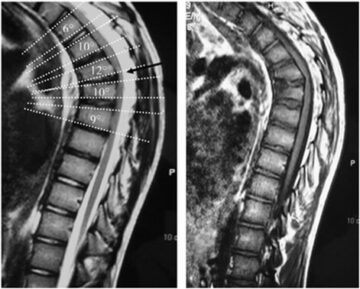

العلاقة بين انزلاق الغضروف في الفقرات الصدرية والقطنية ومرض شويرمان: الأسباب الخفية والأعراض المبكرة يُعاني بعض الأشخاص من آلام شديدة في منتصف وأسفل الظهر تمتد أحيانًا إلى البطن أو الفخذين، ويكتشف الأطباء بعد الفحص

تقوس الظهر عند الأطفال والمراهقين: الأنواع، الأسباب، وأحدث طرق العلاج الفعّالة تقوس الظهر، أو ما يعرف بالتحدب أو القتب، هو انحناء مفرط في الجزء العلوي من العمود الفقري نحو الأمام. قد يكون خفيفًا وغير